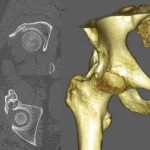

As lockdown was enforced from March 23, 2020, in COVID-19 pandemic, restricting mobility and because of fear of contracting COVID, she did not attend OPD. Telephonic conversation was done to know her condition and it was found satisfactory. Patient physically reported at the end of 3rd month. X-ray of pelvis with both hips was taken which showed well-advanced stage of union. We wanted her to start weight bearing on the left lower limb (and no weight bearing on right lower limb) but she was apprehensive to use crutches because of post-injury discomfort in right shoulder. She started this in 4th month as per telephonic conversation. After 6 months from the surgery, she was readmitted in our hospital under the nephrology unit with reduced hemoglobin. She was treated and two units of packed cell were transfused. Her X-ray showed fractures well united (Fig. 5) and she could walk without support. She was asked to follow-up at 3 months interval. At last follow-up of 9 months her X-ray showed well united fracture in both AP and lateral view (Fig. 6a, b, c) and she had good range of movement in both hips.

Simultaneous fracture neck of femur on the one side and intertrochanteric fracture on the other side is one of the rarest patterns of injury. We did not find any report about such injury in English scientific literature. In bilateral cases, generally the mode of injury is high velocity trauma in young or trivial fall with secondary bone disease. Our patient had a history of chronic kidney disease Stage IV and she fell from standing height. Managing this case was very challenging as she had simultaneous bilateral proximal femur fracture and more so one of them was fracture neck of femur. At the patient’s age of 41 our goal was to preserve the head and fix the fracture. She was managed by a multidisciplinary team comprising of orthopedic surgeon, general physician, nephrologist, anaesthesiologist, physician, and physiotherapist. We planned for single stage fixation to start mobilizing the patient as early as possible. The intertrochanteric fracture was fixed first with dynamic hip screw. Fracture neck of femur was fixed with three cannulated screw after satisfactory closed reduction. One of the three screws used was short reach 16 mm derotation screw which also helped in achieving additional compression at femoral neck fracture site. Two major complications associated with fracture neck of femur following osteosynthesis is nonunion and avascular necrosis of femoral head, which is estimated at 10–30% and 15–30%, respectively, if treated within 24 h [9,10]. As our case had multiple comorbidities, fixation was done after 1 week, after obtaining fitness for surgery, thereby increasing the chances of the complications. Fixation of femoral neck fracture using three cannulated screws is preferred method as it affords adequate stabilization [11]. In our case, the preferred method was used. Due to COVID, we could not follow up the patient at regular intervals, but she was always under our consultation over telephone. At 9 months follow-up she could walk independently with good functional outcome, and her X-rays showed well united fracture and there was no evidence of avascular necrosis.